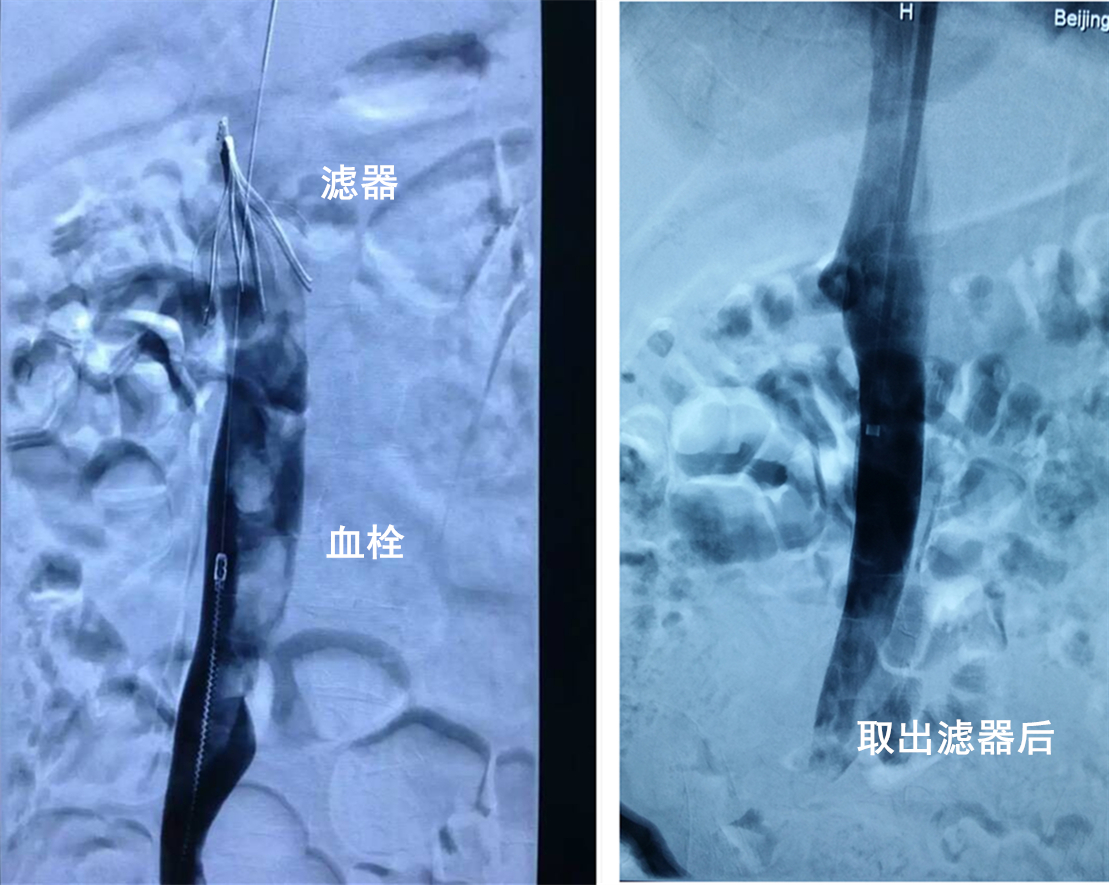

分析下肢深静脉血栓形成的背景,考虑患者的年龄尚年轻,抗凝禁忌,患者插管带呼吸机的危重病情等,血管外科先采取了保守治疗——通过微创手术给患者植入一枚可取出型下腔静脉滤器,预防可能致命的肺栓塞。

经过2周的重症支持治疗,患者脑出血稳定,全身情况得到有效控制,但考虑到外伤休养需长期卧床,且患者有深静脉血栓形成病史,血管外科紧密跟踪治疗,复查彩超时发现血栓发展已满布下腔静脉及髂静脉,一直到达植入的滤器下方,医师在庆幸植入滤器预防了肺栓塞、保住了一条生命的同时,另一个难题来了,这些血栓如何处理?

由吴巍巍主刀,通过微创腔内治疗,机械血栓抽吸导管直接伸入血栓部位进行抽吸,复查造影可以观察到静脉内的血栓被清除,患者的右下肢及下腔静脉的血流恢复了正常,腿部的肿胀也逐渐消失。经过10天的抗凝治疗,患者再次复查彩超,右侧下肢静脉血流恢复正常,下腔静脉内已无血栓阴影,拔除滤器的时机到了,再次造影右侧髂静脉及下腔静脉内血栓,此后患者可放心接受抗凝治疗了。